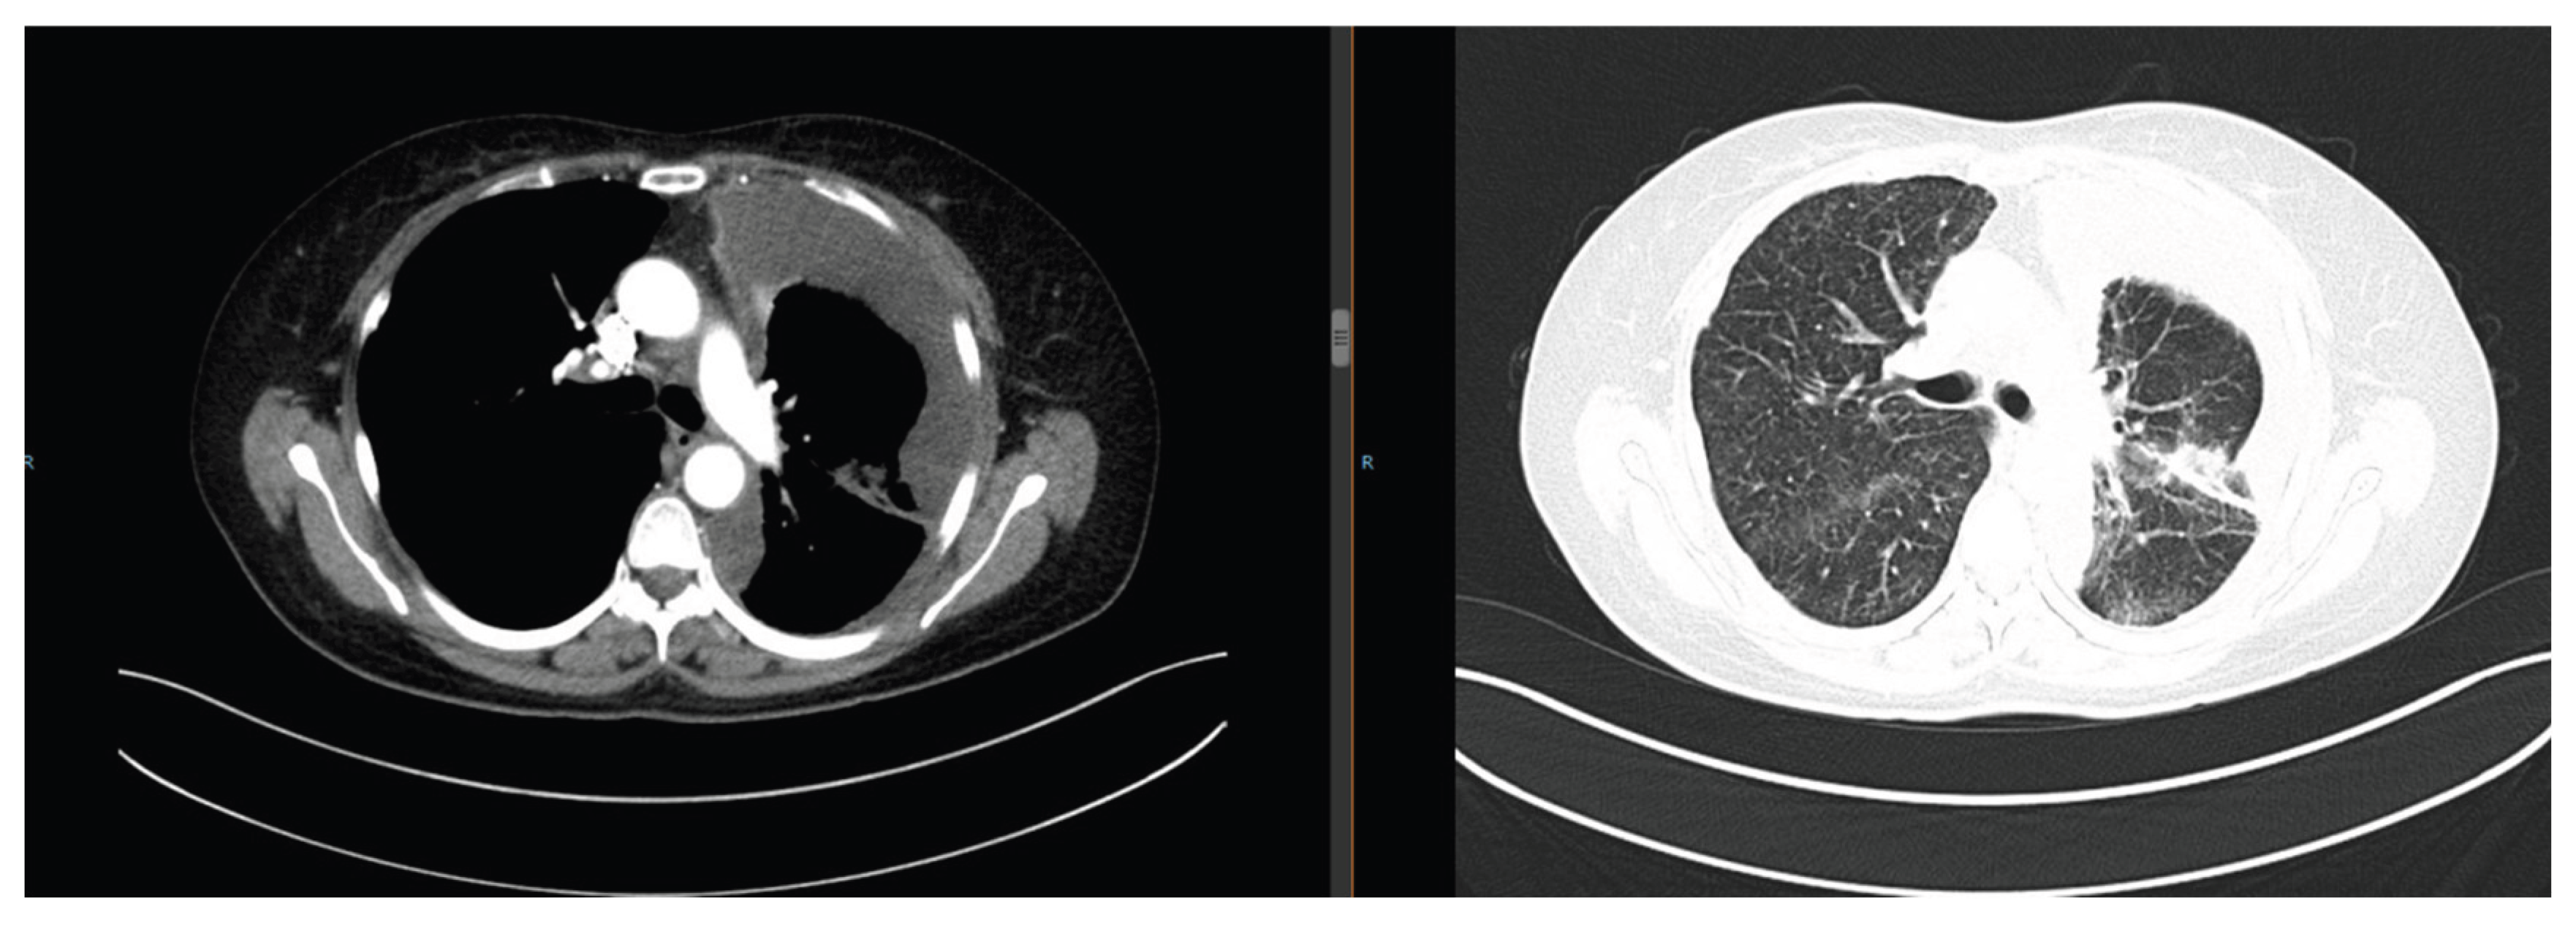

Sixteen months after gefitinib treatment, the pulmonary nodules enlarged (maximum diameter: 4.2 cm) with new lesions (Figure 4), indicating TKI resistance. Repeated biopsy and NGS detected a RET fusion mutation. Due to financial constraints, she refused cabozantinib (a RET inhibitor) and received 6 cycles of pemetrexed + carboplatin chemotherapy combined with anlotinib (anti-angiogenic therapy). The disease remained stable (SD), followed by anlotinib maintenance therapy for 19 months.

Figure 4. Chest CT on January 16, 2021: Enlargement of pulmonary nodules (maximum diameter 4.2 cm) with new lesions.